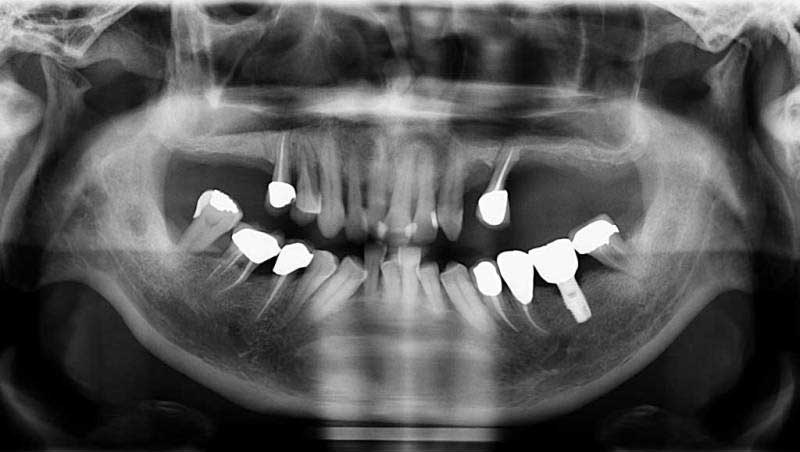

鼻竇增高術術後康復